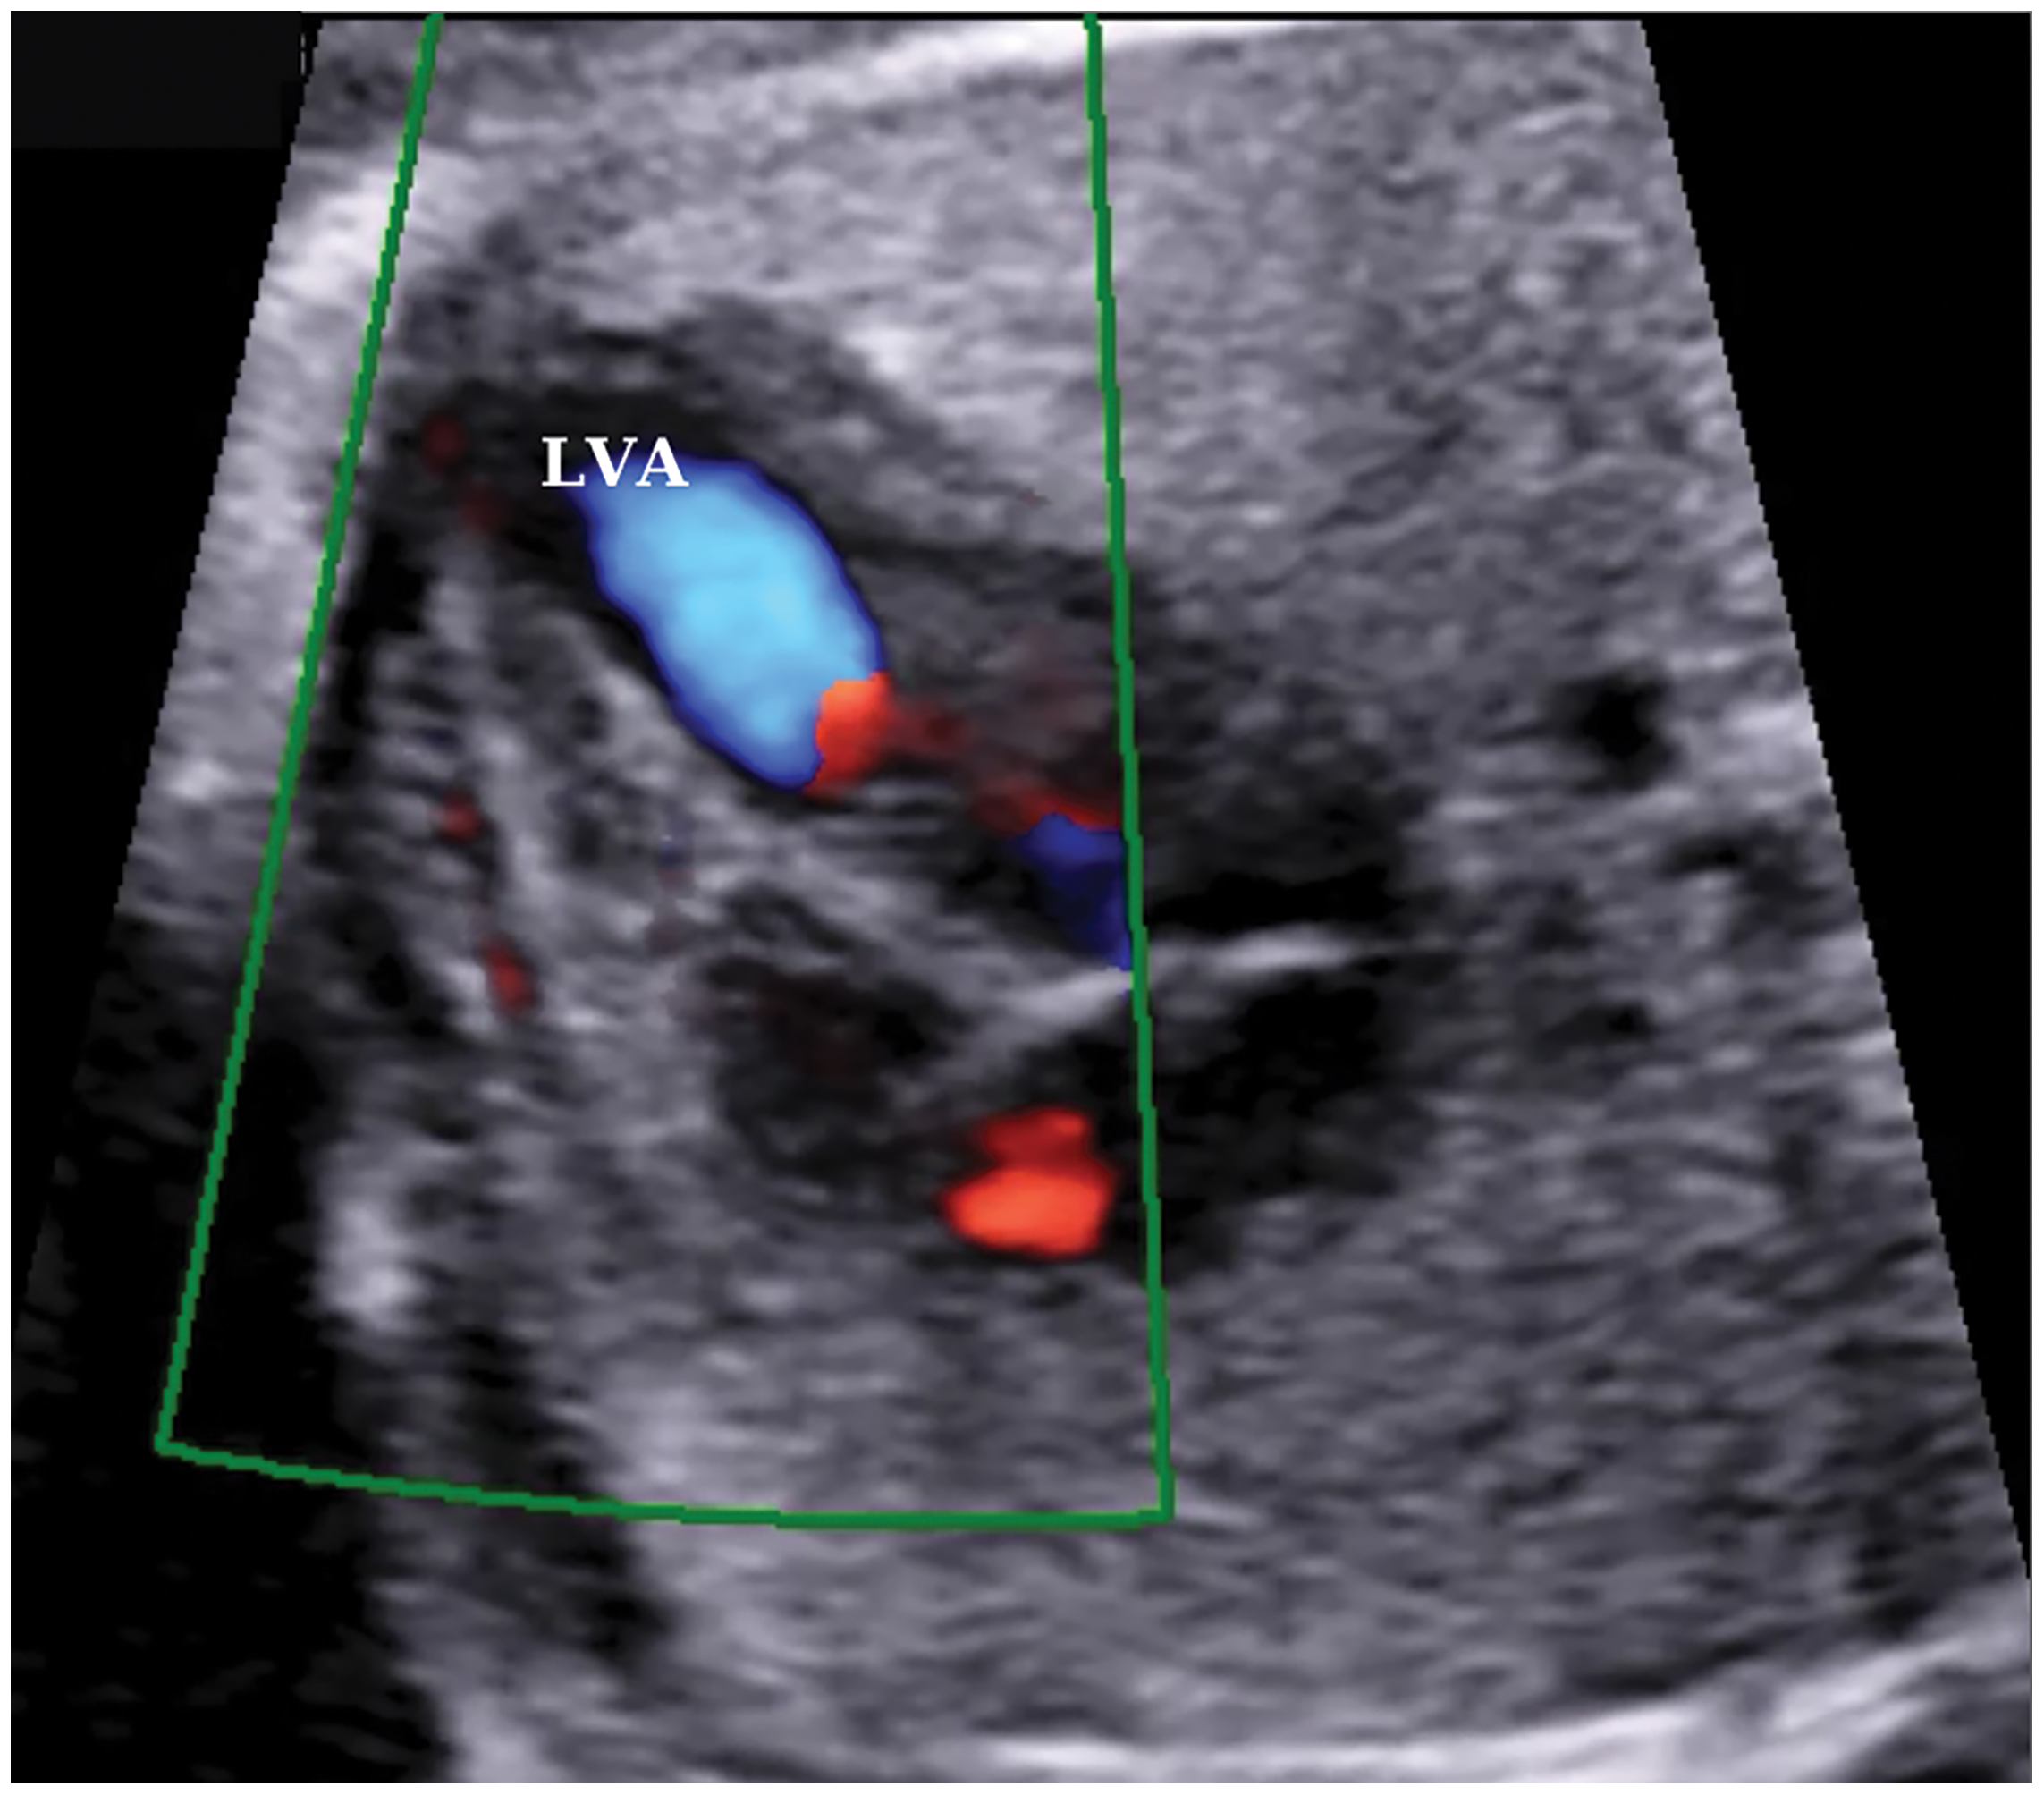

Color Doppler ultrasonography showed an aberrant fibrous band in the LV and turbulent flow during systole, which was thought to be related to this band (Fig. 3).

Figure 3: A color doppler ultrasound image of turbulent flow in the left ventricle at 24 weeks of gestation. LVA, left ventricular aneurysm